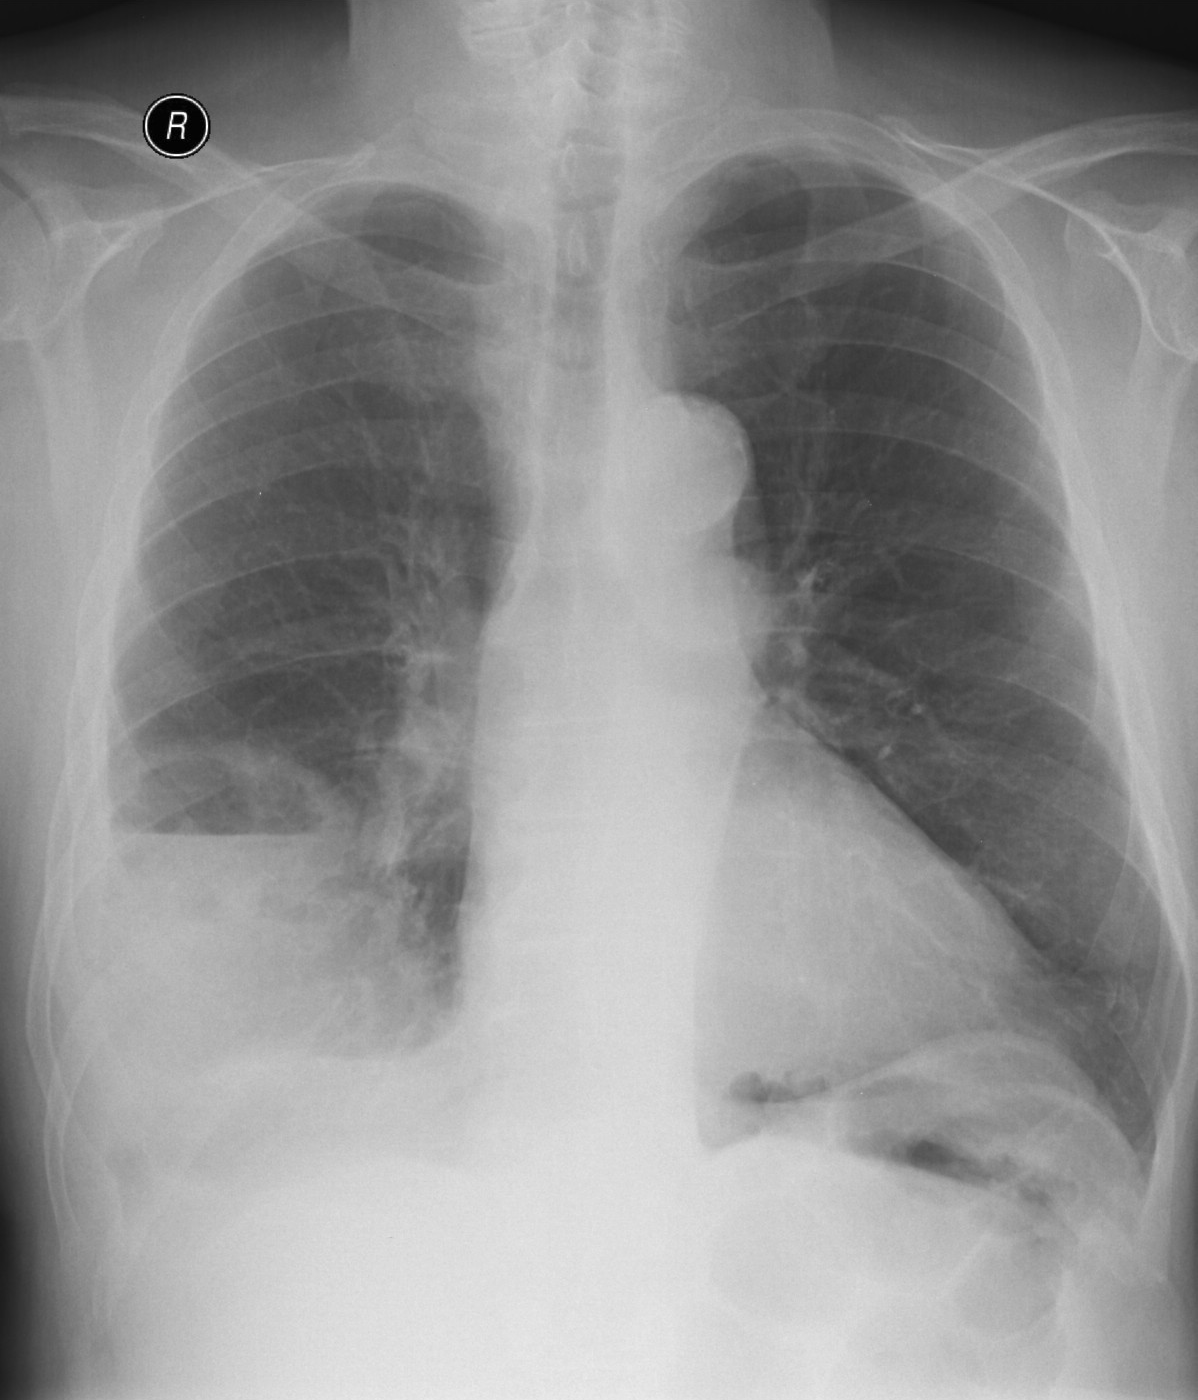

23. Pulmonary metastases, bidirectional (PA and right lateral) plain chest radiograph.

51 year old woman, endometrial carcinoma. Numerous ring shadows bilaterally in basal dominance (max. appr. 12 mm). Left pleural effusion of one finger wide.